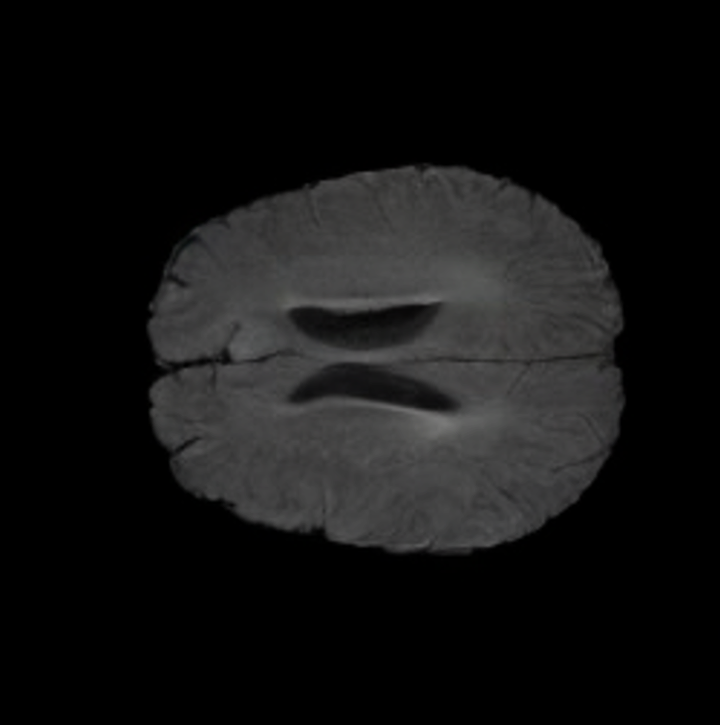

Notably, X-Diffusion achieves state-of-the-art dB for a few input slices while baselines require more than 60 input slices to achieve similar performance (Figure 7). The margin is more than 12 dB PSNR for the 1-slice input in both the BRATS and the UK Biobank benchmarks (see Table 1 and Figure 6). For reference, two randomly sampled MRIs from UK Biobank would have a PSNR of 15.95 dB 0.36 (on 4800 randomly sampled examples). Omitting the preprocessing step of alignment DXA to MRI, leads to a drop of PSNR on average by 2.87 dB (29.01 dB 26.14 dB). The slices from 3D reconstructed volumes at varying depths and axis of rotation, visually match the ground truths for both brain and whole-body scans (see Figures 4 and 5 left). We also plot the error map (Figure 3) and the spread of the error (Figure 5 right) of such X-Diffusion generations to highlight the differences with the ground truth MRIs.

The comparison of generated MRIs versus reference MRIs suggest a nearly perfect preservation of brain volume (in mm3) with median volume of reference MRIs of versus generated MRIs (see an example of brain generation in Figure II).